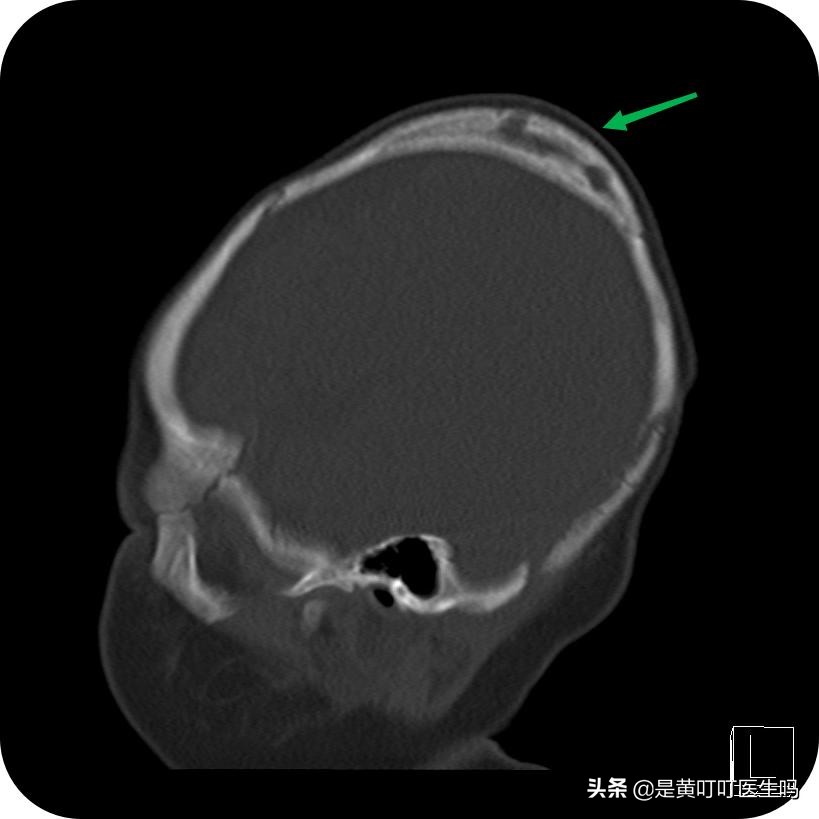

- 偶尔能见到顽固的产瘤,长时间不消退,边缘骨化,像鸡蛋壳一样。所以即使产瘤对宝宝没什么危害,当产瘤长时间没有消退,也应该及时就诊。

产瘤边缘骨化